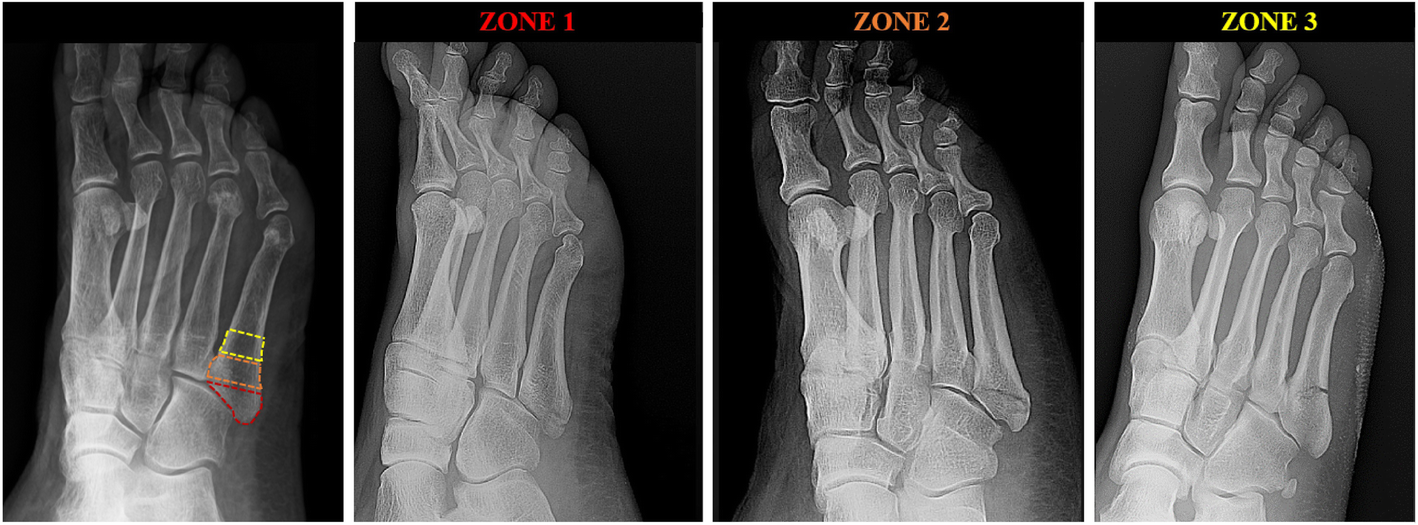

A retrospective observational analysis was performed. Patients diagnosed with fifth metatarsal base fractures between March 2016 to December 2018 were selected. Inclusion criteria were: age at presentation between 18 to 85 years-old and a twisting-type injury as a causative mechanism. Patients with additional fractures involving the foot and/or ankle, forefoot and/or hindfoot deformity, connective-tissue and/or rheumatic diseases, primary tumor or secondary localization, state of pregnancy were excluded. Electronic medical records were searched for sex, age, height, weight, mechanism of injury. Plain radiograph study (Anteroposterior, Oblique and Lateral view) were obtained and classified according to Lawrence and Botte classification (Fig. 1). Patients were classified based on BMI: < 20 kg/m2: underweight, between 20 and 24.9 kg/m2: normal weight, between 25.0 and 29.9 kg/m2: overweight, 30 kg/m2 and above: obese [6]. Statistical analysis was conducted using R V 3.4.4 (R Core Team (2018). R: A language and environment for statistical computing. R Foundation for Statistical Computing, Vienna, Austria [12]. Continuous variables were reported as mean ± standard deviation. Repeated measures design Analysis of Variance (ANOVA) and Tukey’s Honest Significant Difference test were used to compare BMI across groups. ANOVA was finally used to investigate the presence of statistically significant differences attributable to age, and Chi squared test was used to investigate the presence of statistically significant differences attributable to sex.

Fig. 1

Radiographic classification of the fractures according to Lawrence and Botte7. The three different zones are based on anatomic landmarks (far left): proximal to the meta-diaphyseal junction involving the tuberosity (zone 1, centre left), between the lines of the intermetatarsal joint between fourth and fifth metatarsal bones involving the meta-diaphyseal junction and the intermetatarsal articular facet (zone 2, centre right), distal to the meta-diaphyseal junction involving the proximal diaphysis (zone 3, far right)